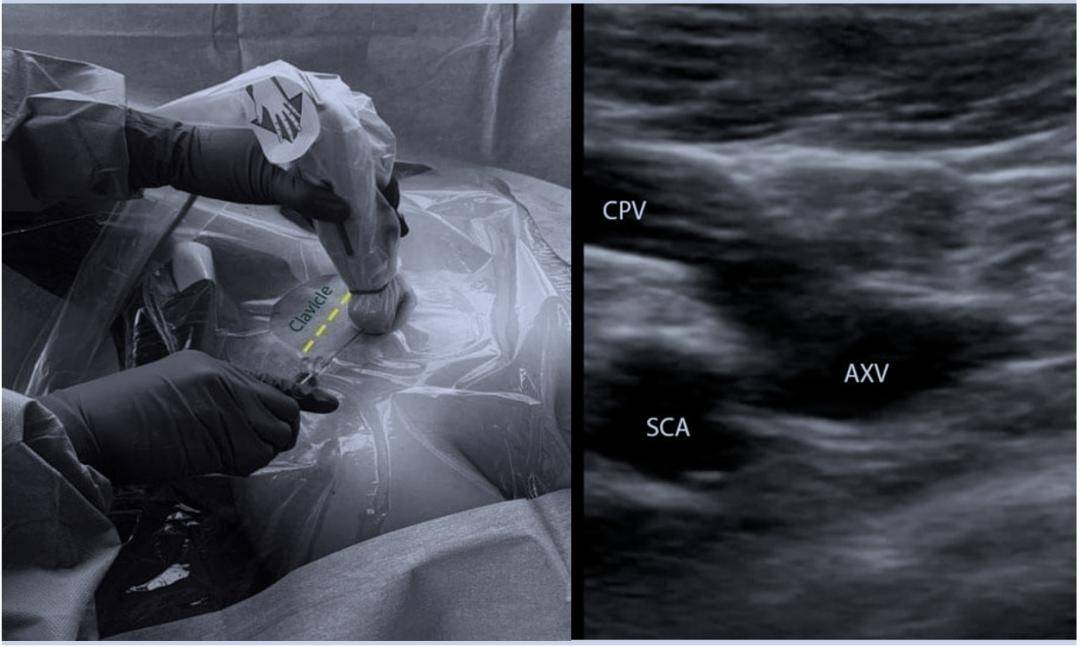

操作技巧 | 超声引导下锁骨下静脉穿刺

图8 锁骨下静脉超声纵切面二维图像参考文献略提问①cvp波形的意义②

超声引导下锁骨下静脉穿刺

实用技术 | 超声引导下锁骨下静脉穿刺置管_视频_导管_动脉